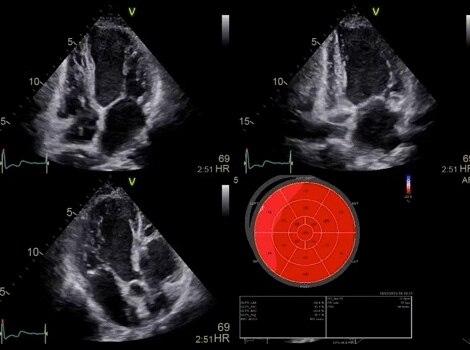

VividTM 系列心脏超声波自动功能成像(AFI)

明确评估左心室功能和心脏功能,提高临床信心。了解更多信息

Vivid 系列心脏超声波

Vivid E95 兼具 cSound 性能,可使 4D 在量化左心室壁运动方面与 2D 一样简单。了解更多信息

Vivid™ 系列心脏超声波自动功能成像(AFI)

明确评估左心室功能和心脏功能,提高临床信心。

Vivid™ 系列心脏超声联合自动定量